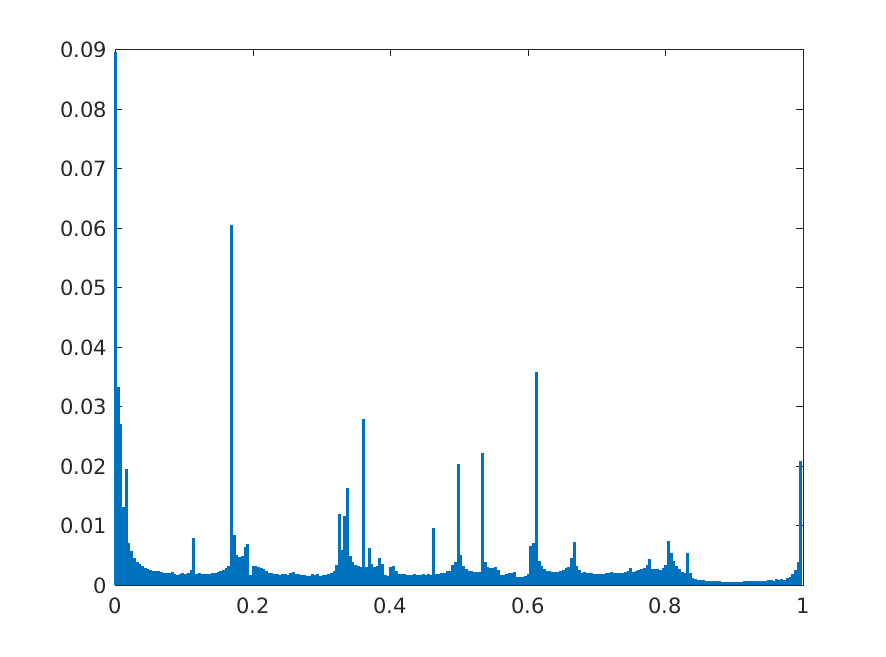

For all these experiments, we found that taking features from earlier layers compared to later layers improve accuracy by 2 to 4 percentage points. Shallow DCN features are often useful for detecting small objects in images [27]. Our findings are similar for chest X-Ray abnormality classification as well. As an example, we are showing the performance obtained by taking features from different layers of ResNet-152 model. The candidate layers are chosen from the 4th, 5th and final stage of the network based on what type of operations they perform. The chosen layers and their corresponding operations are listed in Table 3. The notation of the layers is based on the pre-trained model obtained from MatConvNet Pre-train Library. We trained five models to detect cardiomegaly using features from each of the layers and the average performance of these features in terms of accuracy, AUC, sensitivity, and specificity for Cardiomegaly detection are shown in Fig. 3. It can be observed that the performance of the final pooling layer (pool5) is degraded compared to the other layers in terms of accuracy, sensitivity and specificity. In particular features from residual connections (res4b35, res5c) and ReLU (res4b35x, res5cx) are considerably better with features from res4b35 providing highest accuracy. Similar observations are made for other ResNet variants, VGG nets and AlexNet.

8 Additional Examples of Localization

In this section we show more examples of localization. Few localization samples are shown in Fig. 11. It can be observed that, in the CXRs with Cardiomegaly (Fig. 11(a) and (b)) a fine localization around the heart is observed. In the normal CXRs (Fig. 11(c) and (d)) such localization is not observed. Rather the lowest probabilities are spread out in the CXR image. It is interesting to note that, the localization algorithm gets low probability where the heart is enlarged during cardiomegaly, but the proportion is small compared to the localization in other areas of normal CXRs. In order to observe the performance of the heat map we computed histograms of heat maps of each of the 100 CXRs in the test set for Cardiomegaly detection and average histograms are shown in Fig. 11(e) and (f) for CXRs with Cardiomegaly and normal CXRs, respectively. It is to be noted that, the histograms include both success and failure cases. It can be observed that, for CXRs with Cardiomegaly the classifier is highly sensitive toward Cardiomegaly detection even under occlusion. This indicates that, the classifier primarily looks for local features in a CXR instead of some feature that is spread out in the entire CXR. However, the classifier is not sensitive toward normal CXRs under occlusion. Rather, the probabilities are spread out in the probability spectrum. After that, we analyzed the failure cases where the classifier is unable to classify the image correctly. Two such examples of failure cases are shown in Fig. 12. The localized CXR shown in Fig. 12(a) contains Cardiomegaly whereas the classifier detects it as normal. However, the localization shows that it localizes around heart quite well despite the in accurate classification. On the other hand, Fig. 12(b) shows an example of normal image which has been classified as Cardiomegaly by the classifier. There is stronger localization around the hear that that is observed for normal images as in Fig. 11(c) and (d), however, like those images the localization is spread out.